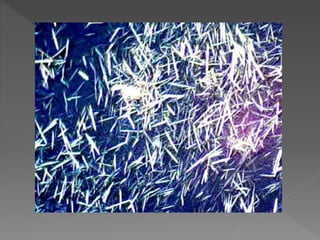

Depósitos medulares intersticiales por cristales de urato en la nefropatía crónica

por uratos.

Los cristales suelen perderse en el procesamiento rutinario del tejido, pero

queda su sombra, las células gigantes multinucleadas que los rodean y la

agrupación particular que adoptan en el tejido. Este hallazgo es relativamente

frecuente en riñones de personas mayores; estos depósitos no suelen producir

insuficiencia renal. (Tricrómico de Masson, X400).